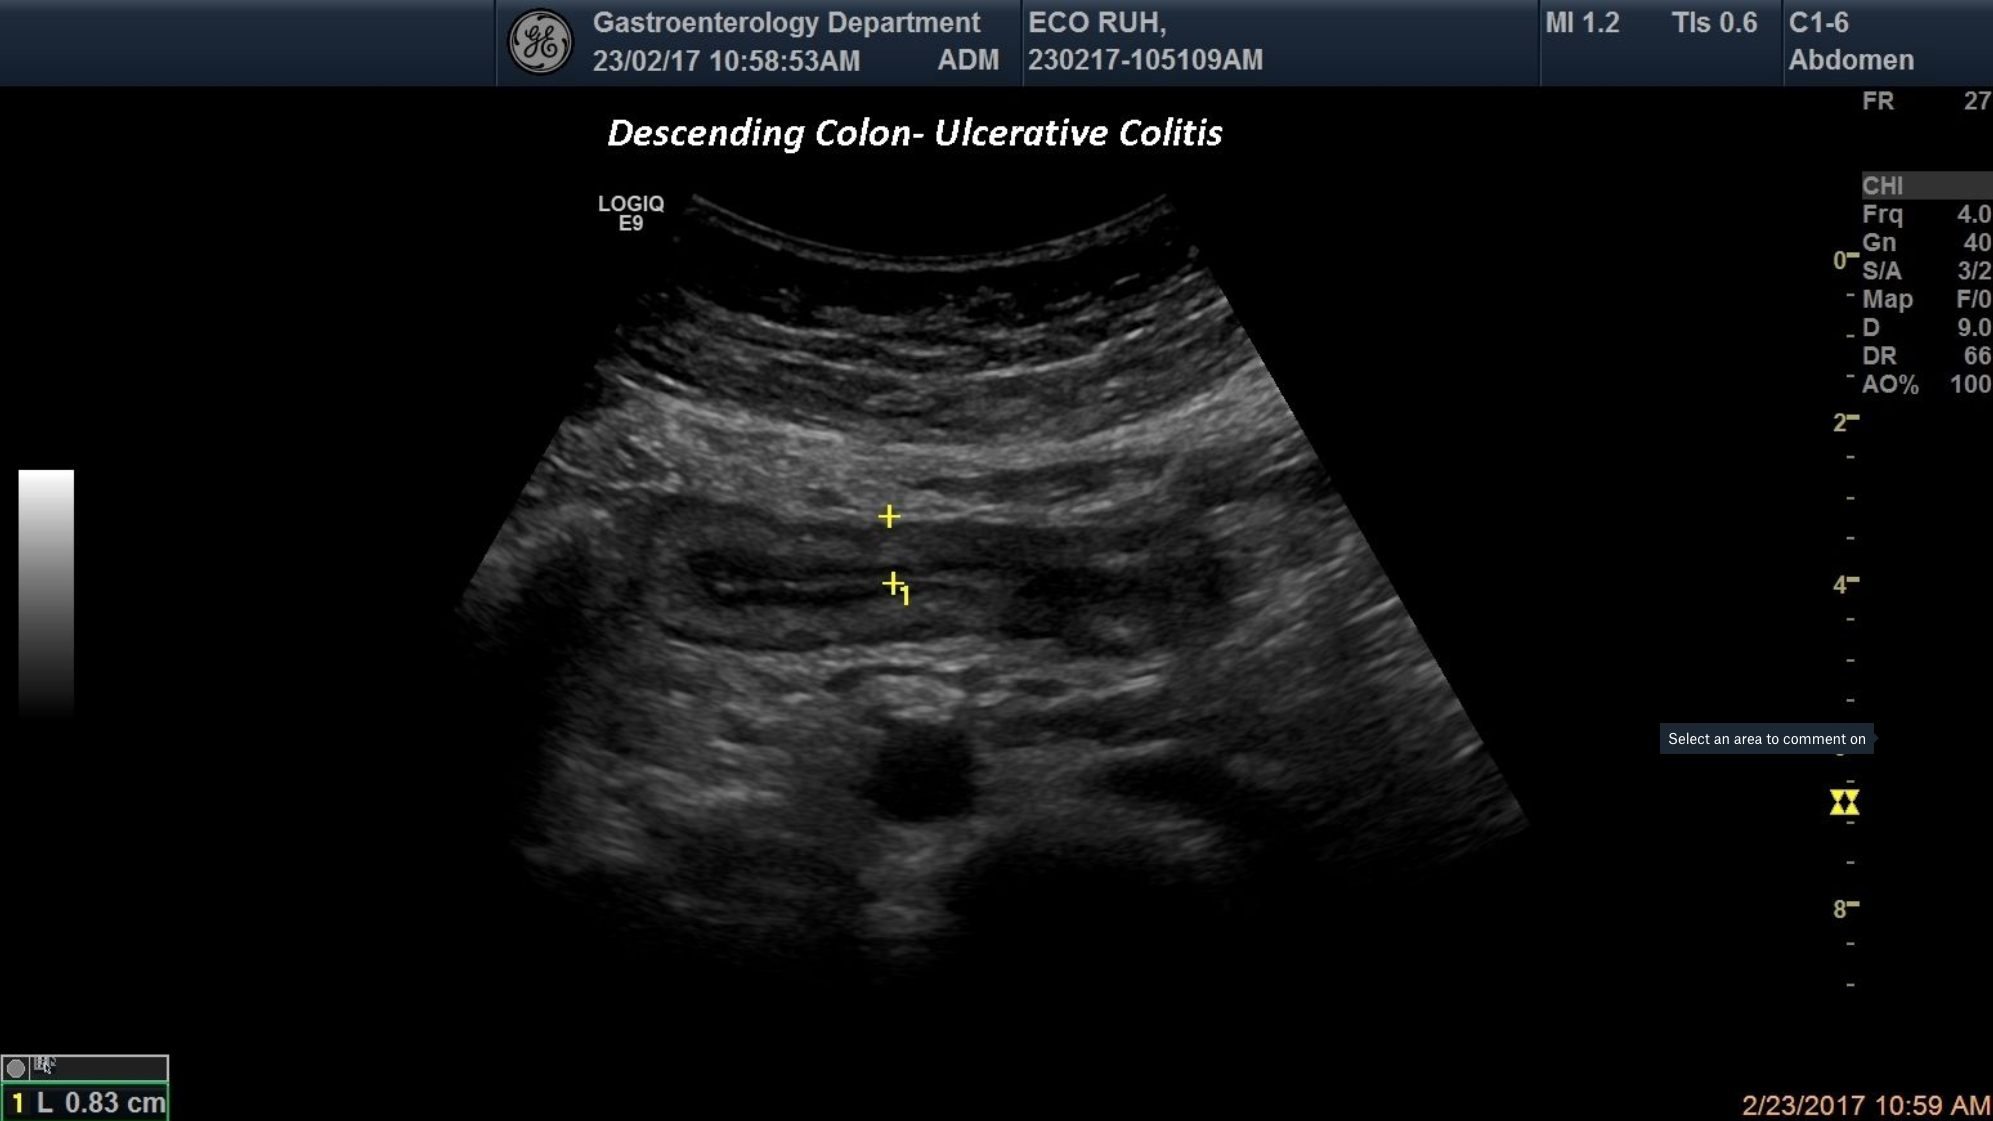

TITLE: Ulcerative colitis-descending colon

A patient with bloody diarrhea and abdominal pain was sent to our department for a checkup. Abdominal ultrasound was performed and depicted a wall thickening of the descending colon and the loss of the multi layer pattern. Later on colonoscopy with biopsy was performed that proved the diagnosis of ulcerative colitis of the descending colon.

Ulcerative colitis, descending colon, wall thickening